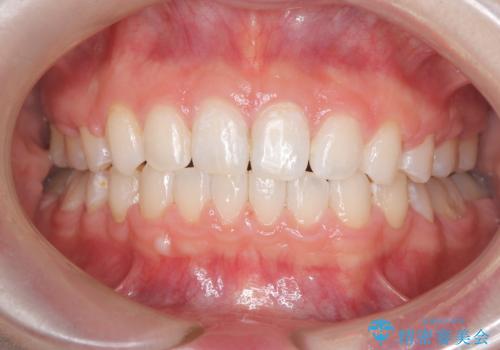

[セラミック治療] 前歯の審美治療に伴う矯正治療